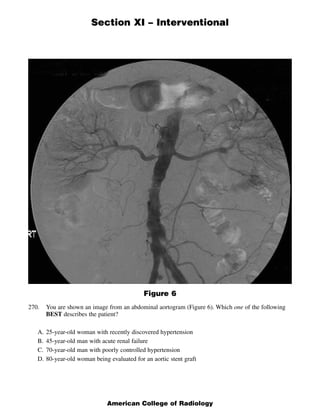

This document contains 5 clinical case scenarios involving interventional radiology procedures (questions 265-269). Each case is accompanied by an image and 4 possible answers. The correct answer is identified and a brief rationale is provided for each case. Question 270-279 continue testing knowledge of interventional radiology with additional multiple choice questions related to procedures, techniques, and disease processes.